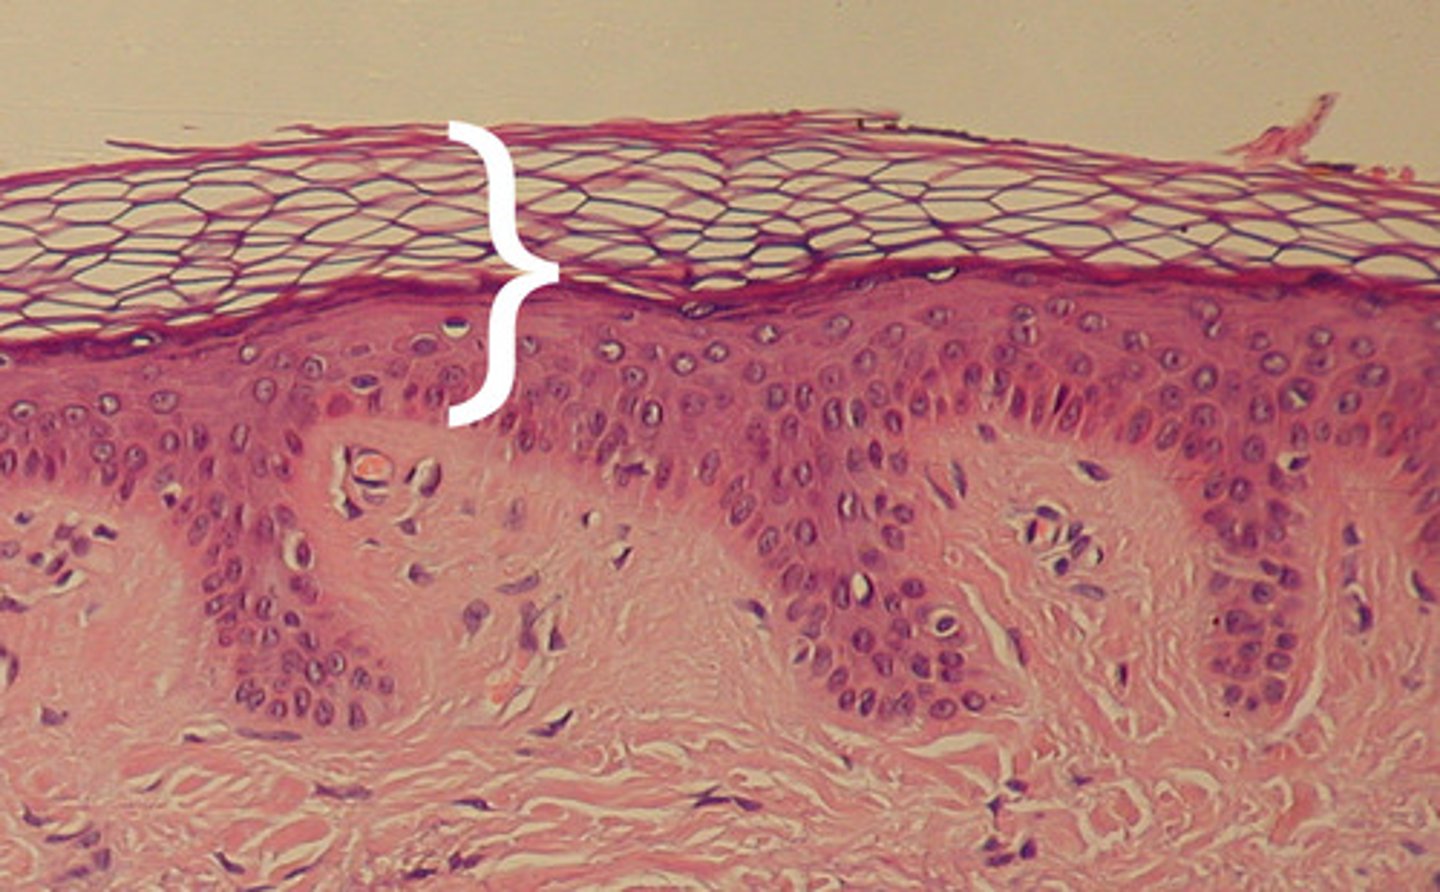

Epidermis

Outer layer of skin

stratum corneum

outermost layer of epidermis

stratum lucidum

Clear, transparent layer of the epidermis under the stratum corneum.

stratum granulosum

a layer of the epidermis that marks the transition between the deeper, metabolically active strata and the dead cells of the more superficial strata

stratum spinosum

stratum basale

the deepest layer of the epidermis consisting of stem cells capable of undergoing cell division to form new cells

Dermis

Inner layer of skin

papillary layer

outer layer of the dermis, directly beneath the epidermis; made of loose connective tissue

reticular layer

The deeper layer of the dermis that supplies the skin with oxygen and nutrients; made of dense irregular connective tissue

dermal papillae

a fingerlike projection of the dermis that may contain blood capillaries or Meissner corpuscles (of touch)